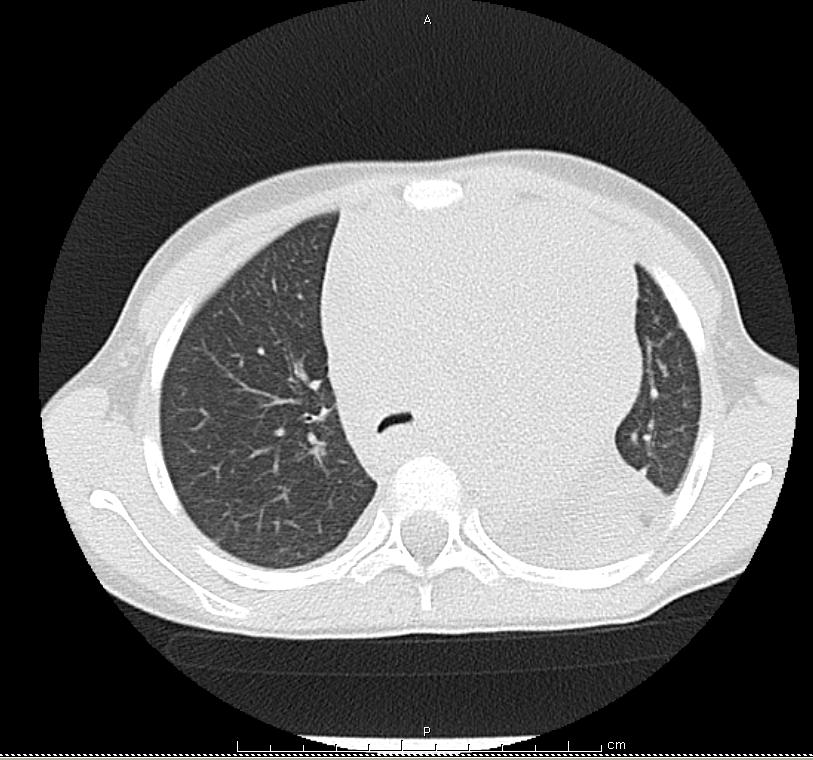

Nel sospetto di una neoformazione a livello del torace si esegue quindi una TC Torace con riscontro di voluminosa massa mediastinica anteriore, paramediana sx, estesa dalla regione laterocervicale inferiore sx fino in sede sovra diaframmatica (diam. Max AP-LL-CC 98X97X169 mm) (Figura 3 e Figura 4). Tale massa, che comprime alla base del collo il lobo sinistro della tiroide e disloca lateralmente l'asse tracheale e l'esofago senza segni di infiltrazione locale, avvolge completamente tutte le strutture vascolari presenti in ambito mediastinico che mantengono comunque una regolare perviet� endoluminale. Viene inoltre confermata la presenza di versamento pericardico e di versamento pleurico a sinistra associato ad atelettasia passiva del parenchima polmonare contiguo. Si esegue inoltre un'ecografia del collo che in sede laterocervicale e sovragiugulare sx apprezza la presenza di tessuto di tipo solido disomogeneo con diametri di circa 3,5x 2,4 cm che ingloba il fascio vascolare del collo e impronta il lobo sx della tiroide, nel cui interno si visualizzano alcuni linfonodi ipoecogeni. Gli altri esami eseguiti (TC Addome, TC Cranio-Encefalo) risultano negativi.Nel sospetto di un'origine linfomatosa, B. viene sottoposta in videotoracoscopia a biopsia della massa il cui successivo referto istologico conferma la diagnosi di Linfoma linfoblastico a precursori T. Viene quindi intrapresa la chemioterapia tuttora in corso.